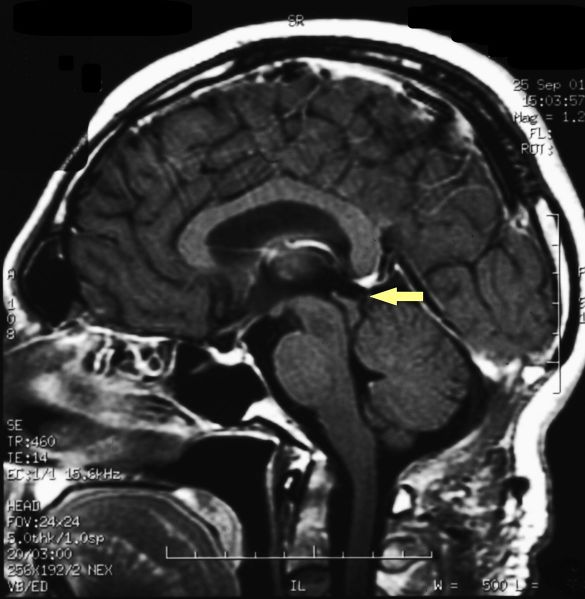

File:Pienal cavernoma post surgery 2.jpeg